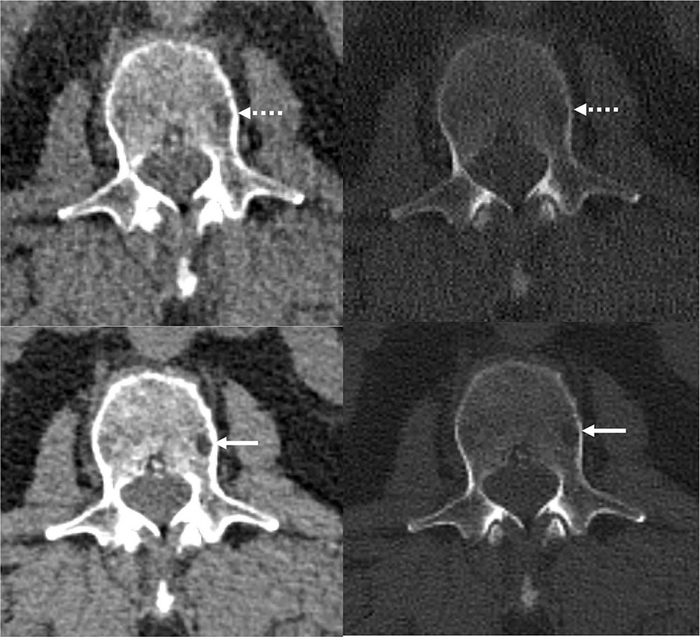

The researchers also applied a deep learning AI technique developed at Mayo Clinic’s CT Clinical Innovation Center to reduce the noise in the very sharp photon-counting images. CT noise refers to an unwanted change in pixel values in the image, often loosely defined as the grainy appearance on cross-sectional imaging. The photon-counting detector CT with deep learning noise reduction demonstrated improvement in visualization and detected more lesions relative to conventional CT.

“We were excited to see that not only were we able to detect these features of multiple myeloma disease activity more clearly on the photon-counting scanner,” Dr. Baffour said, “with deep learning denoising techniques that allowed us to generate thinner image slices, we were able to detect more lesions than on the standard CT.”